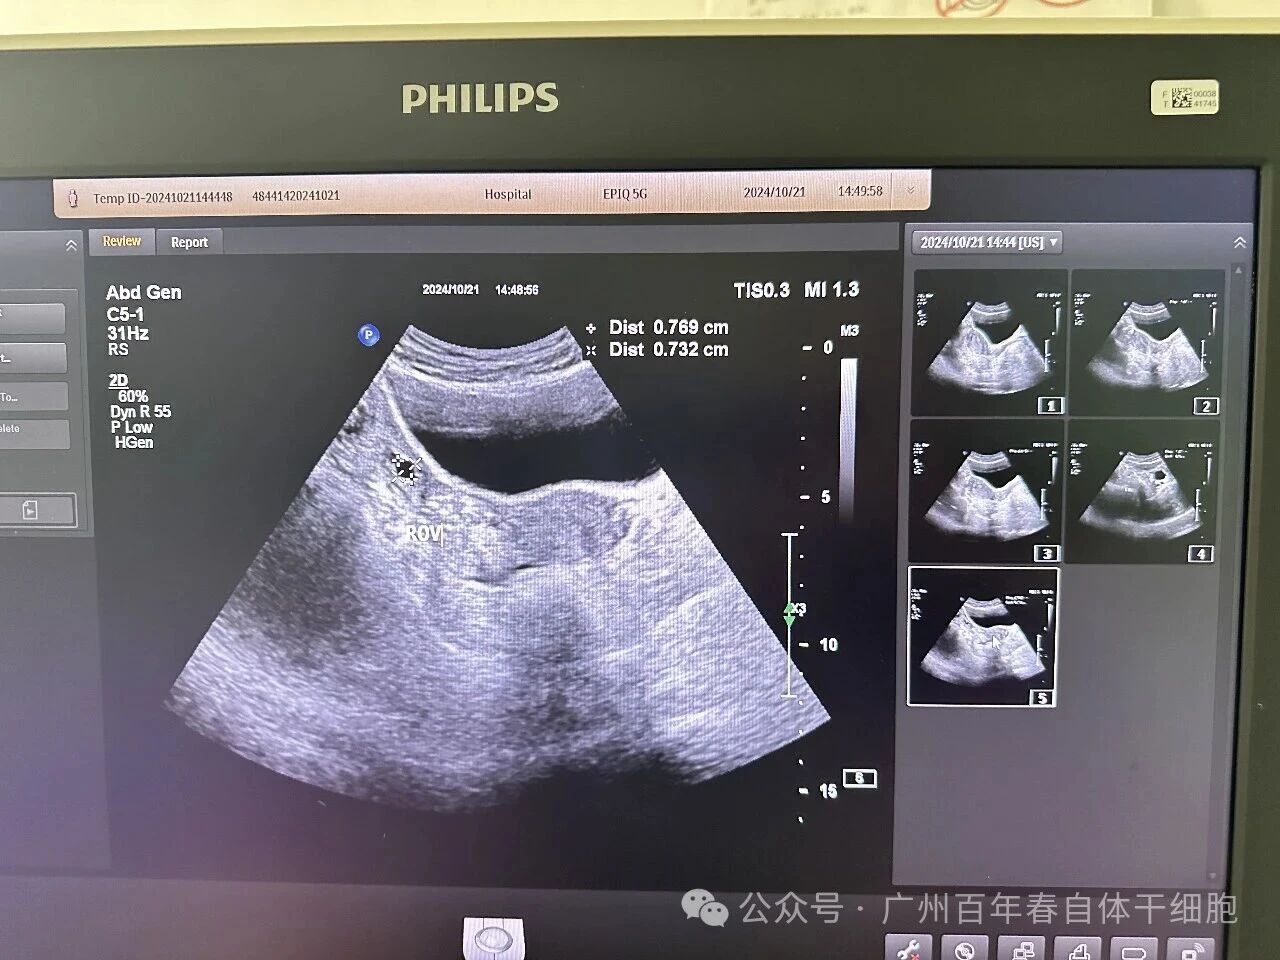

△保健后45天B超复查

盆腔积液:2.19cm的积液完全消失,卵巢结构清晰可见